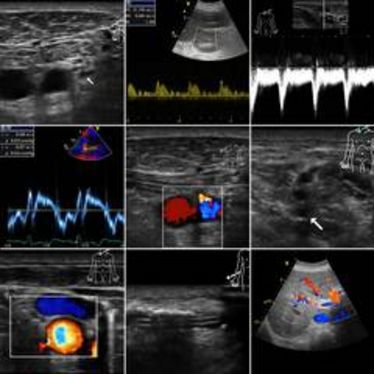

2. Münsteraner Ultraschall-Kurs

2. Münsteraner Ultraschall-Kurs

2. Münsteraner Ultraschall-Kurs

2. Münsteraner Ultraschall-Kurs

International Summer School of Ultrasound

International Summer School of Ultrasound

Sonographie-Aufbaukurs: Weiterführende Differentialdiagnostik des Feten

Sonographie-Aufbaukurs: Weiterführende Differentialdiagnostik des Feten

Doppler-Sonographie Schwangerschaftsdiagnostik - Interdisziplinärer Grundkurs

Doppler-Sonographie Schwangerschaftsdiagnostik - Interdisziplinärer Grundkurs